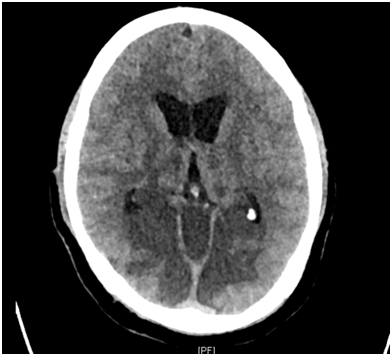

- Radiology: The pattern of infarcts follows the level of involvement of the unpaired basilar artery and its branches. Sixteen patients with demonstrated top of the basilar syndrome found infarcts distributed between the thalamus, midbrain, pons, cerebellum, and occipital lobe. Bilateral thalami were seen to be involved in seven cases. CT evidene of a hyperdense basilar artery usually demonstrates a filling defect on angiography confirming the site of occlusion5 (Figures 1a, 1b & 2).

Figure 1a Hypodensity in the brainstem and adjoining superior cerebellar peduncle, with dense basilar sign.

Figure 1b Hypodensity in the brainstem, bilateral cerebellar hemispheres, evidence of obstructive hydrocephalus, suggestive of basilar artery thrombosis.